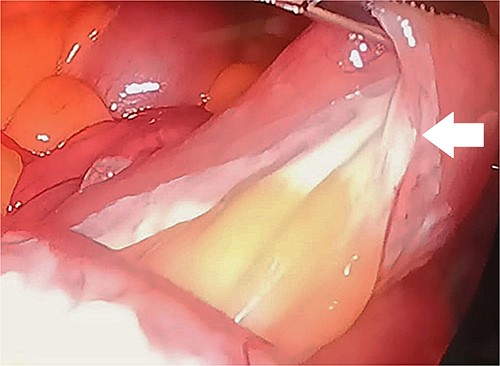

Upon examination, she had normal vital signs. Abdominal examination revealed a mildly distended and generally soft abdomen with tenderness in the upper quadrants. Bowel sounds were reduced. Lab tests showed a significantly elevated C-reactive protein level of 265 mg/dL (normal range: <0.3 mg/dL). Axial CT scan revealed mesenteric edema, jejunal wall thickening, surrounding fat stranding, and an enlarged mesenteric lymph node (Fig. 2). An emergent diagnostic laparoscopy revealed a mildly dilated viable jejunal loop, ~16 cm in length, located 10-cm distal to the ligament of Treitz. Additionally, a milky jejunal mesentery and a moderate amount of chalky ascitic fluid in perihepatic, perisplenic, and pelvic regions were observed (Fig. 3). Fluid analysis confirmed chylous ascites with a triglyceride level of 320 mg/dL (normal range: <110 mg/dL). Histopathological analysis of an excisional biopsy revealed abnormally dilated lymph vessels, leading to a diagnosis of cavernous mesenteric lymphangioma with chylous ascites. Surgical excision was not pursued because of the patient’s aggressive metastatic CUP state. She had an uneventful postoperative course, discharged on the fourth day, and was referred for follow-up with the oncology team for palliative chemotherapy.

Axial view CT showing prominent mesenteric edema with jejunal wall thickening and surrounding fat stranding (arrow). An enlarged mesenteric lymph node can also be seen (circle).